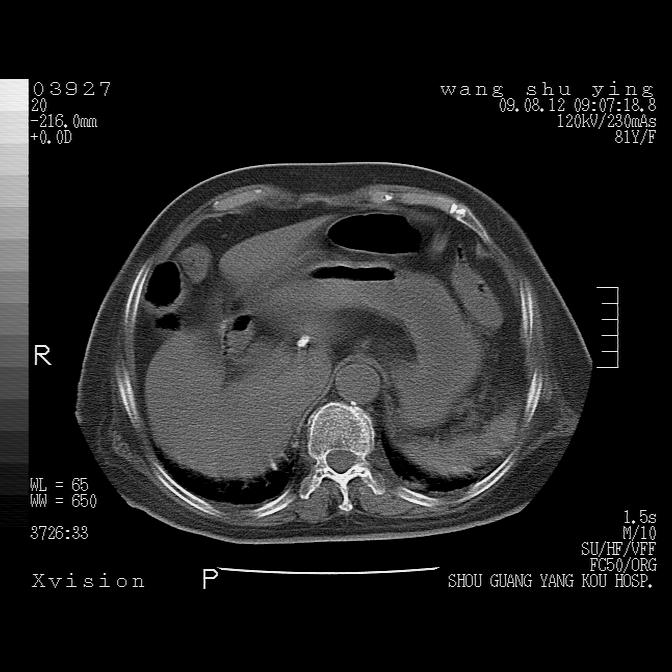

以下是引用随光逐影在2009-8-12 19:42:00的发言:[br]1)两肺感染性病变伴双侧胸膜肥厚。2)不排除左侧甲状腺腺瘤。3)肝脏占位性病变;建议行进一步检查。